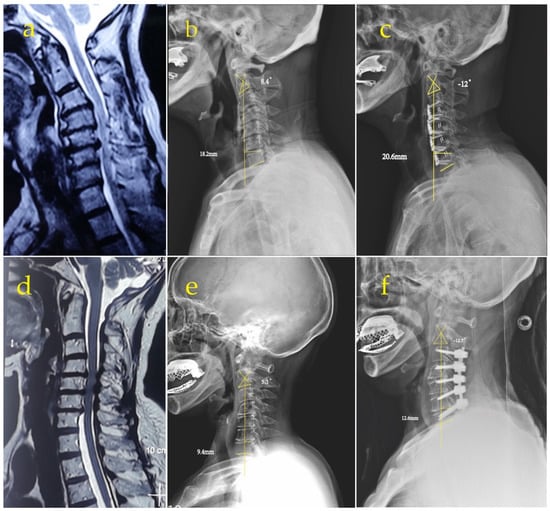

Anterior Group: the anterior approach surgery was performed according to Smith et al. [15]. All patients underwent general anesthesia and neurophysiological monitoring and were placed in a supine position with the neck slightly posteriorly extended. An oblique incision was made at the internal border of the sternocleidomastoid muscle to expose the target segment. The intervertebral space with the most significant compression was treated first, and the intervertebral space was propped open to completely remove the degenerated disc tissue, cartilaginous endplates, and hyperplastic bone, preserving the bony endplates. The posterior edge of the vertebral body was carefully abraded with a high-speed burr, and the posterior longitudinal ligament was severed and adequately decompressed to the bilateral Luschka joint in patients with comorbid radicular symptoms. A low-profile cage (carmen Integral Cervical Interbody Fusion System, Sanyou, Shanghai, China) (Figure 1) was implanted with artificial bone and some autologous bone, then inserted into the decompressed intervertebral space. Other involved levels were treated using the same method.

Figure 1. Low-profile cage (Shanghai Sanyou, carmen Integral Cervical Interbody Fusion System).